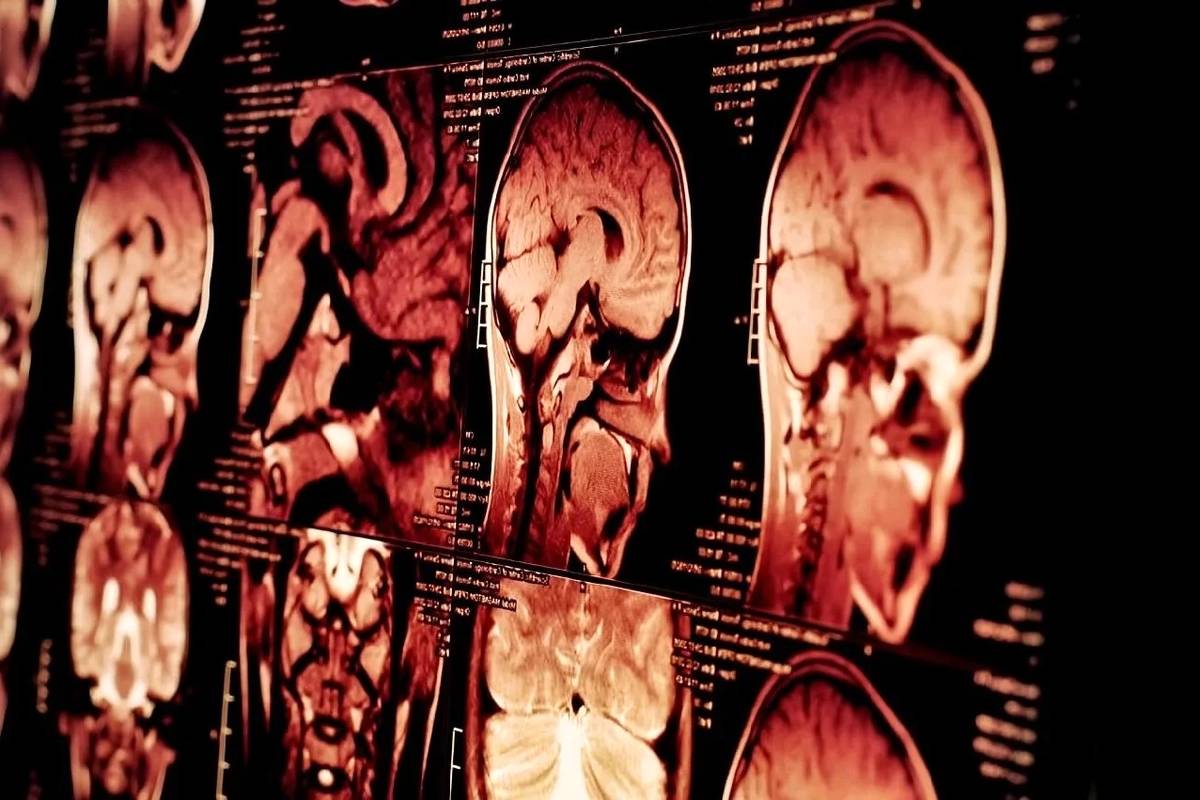

پژوهش جدید: مردان ۳ برابر بیشتر در معرض خطر مرگ ناشی از ضربه مغزی هستند

محققان با بررسی داده‌های مرگ‌ومیر در ایالات متحده احتمال مرگ ناشی از آسیب‌های مغزی تروماتیک (TBI) یا ضربه مغزی را در مردان و گروه‌های دیگر نشان دادند. آنها دریافتند که احتمال مرگ ناشی از TBI در مردان ۳ برابر بیشتر از زنان است.

براساس گزارش ScienceDaily، محققان مرکز کنترل و پیشگیری از بیماری آمریکا (NCIPC) دریافتند که مردان بیشترین احتمال مرگ ناشی از TBI را دارند: بیش از 3 برابر زنان. یافته‌ها نشان می‌دهد که خودکشی شایع‌ترین علت مرگ‌های مرتبط با TBI است و به دنبال آن سقوط‌های غیرعمدی قرار دارد.